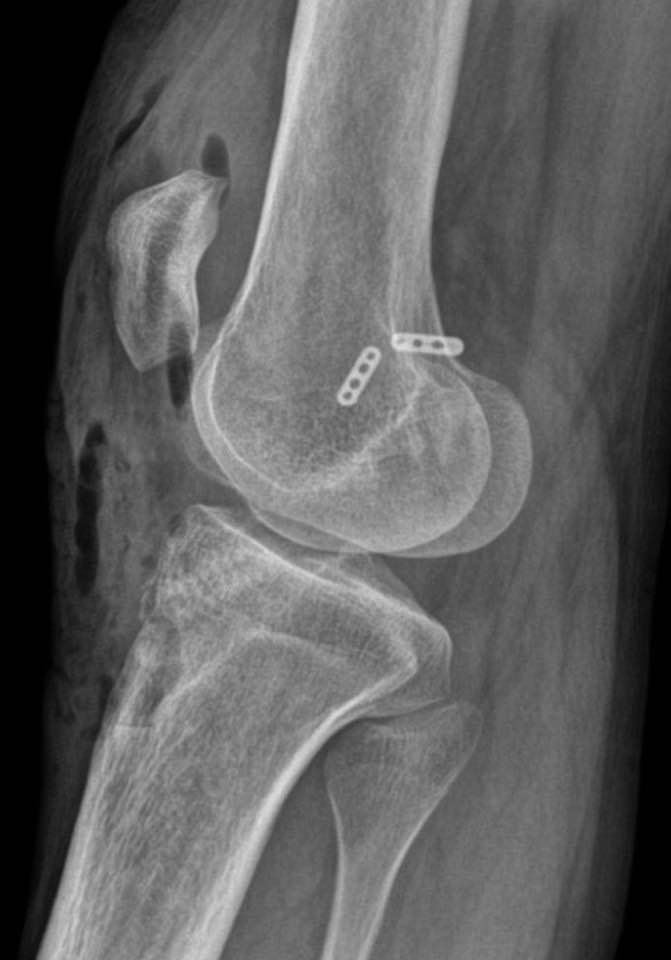

Mala posición, fácil revisión. Reconstrucción de LCA en falla de plastia primaria, utilizando autoinjerto de HTH con técnica clásica, respetando trayecto del nervio Safeno. Tenosuspension femoral con BTB tighrope de Arthrex* más interferencia tibial con tornillo biocompuesto 10 mm de Arthrex*.